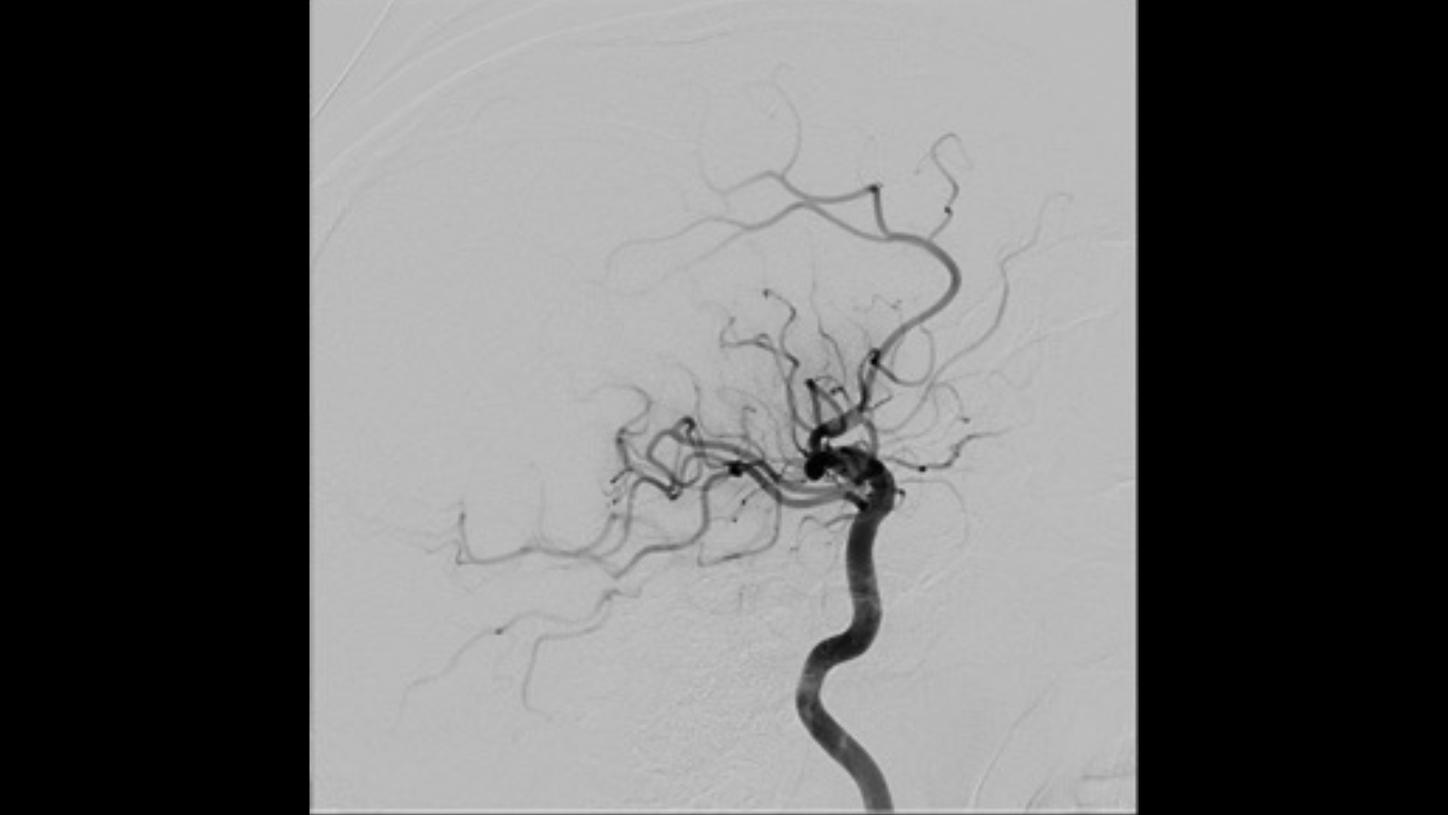

Lateral projectionFollow-up DSA to visualize treatment success

AP projection

Lateral projection